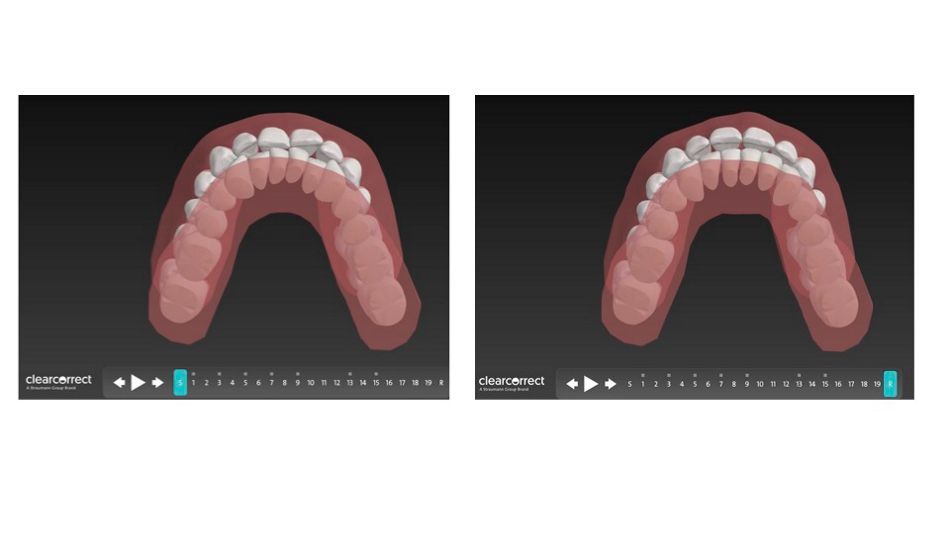

Zunächst einmal wurde der Patient mit dem TRIOS 4 Scanner intraoral gescannt. Es wurden 8 kieferorthopädische Fotos aufgenommen. Diese Daten wurden unter kieferorthopädischen, funktionalen und ästhetischen Aspekten analysiert [1,2,3,4] und in das ClearCorrect Portal hochgeladen, wo eine Fallplanung wenige Tage später vorgeschlagen wurde.

Das Hauptziel war es, die Oberkieferfront, die aufgrund des tertiären Engstandes retrudiert war, wieder aufzurichten, sowie durch die Retrusion und Intrusion der Unterkieferfront, soviel Overjet zu schaffen, dass der Unterkiefer durch Autorotation in eine bequemere Position gelangen kann. Gleichzeitig wurde durch bukkalen Wurzeltorque der oberen Prämolaren, der Oberkiefer leicht expandiert, um einen ästhetischen Bukkalkorridor zu erlangen und dem Unterkiefer etwas mehr Platz in der Transversalen zu gewähren [4].

Die ersten Aligner wurden eingesetzt. Es waren insgesamt 19 Aligner Sets für die erste Phase der Behandlung vorgesehen. ASR wurde in Höhe von 2,4mm im Unterkiefer appliziert, um genug Overjet durch Retrusion der Unterkieferfront zu gewährleisten und gleichzeitig den Frontzahnengstand zu beheben. Der Oberkiefer benötigte nicht mehr als 0,5mm ASR. Es wurden vertikale Attachments auf 14, 13, 21, 24, 25, 33, 31, 32 angebracht, um Rotationen und bukkalen Wurzeltorque der Incisivi und Prämolaren zu ermöglichen, wodurch der Zahnbogen wieder als Ganzes aufgerichtet werden sollte. Es wurde nur ein horizontales Attachment auf 31 appliziert, um dessen Intrusion zu erleichtern.

Nach 19 Aligner Stufen, wurden alle bisherigen Attachments entfernt und für die Revision gescannt, um etwas mehr Overjet zu schaffen. Weitere 11 Aligner Sets wurden geplant und vom Patienten getragen. Um Zahn 11 körperlich besser bewegen zu können, wurde ein 3 x 1 mm horizontales Attachment angebracht. Weitere 0,9mm ASR wurden im Unterkiefer durchgeführt, um die Unterkieferfront weiter zu retrudieren. Im Oberkiefer wurde lediglich zwischen Zahn 11,21 0,3mm ASR appliziert, um das verbleibende schwarze Dreieck zu schließen. Die Revision sollte nie als Fehlversagen eingeordnet werden, sondern vielmehr als Möglichkeit ein hundertprozentiges kieferorthopädisches Ergebnis für den Behandler und Patienten zu erreichen.

Fallplanung vorher und nachher hinsichtlich der Envelope of Function

Fallplanung vorher und nachher bezüglich der inzisalen Inklination und der daraus resultierenden restriktiven Envelope of Function und dessen Korrektur.